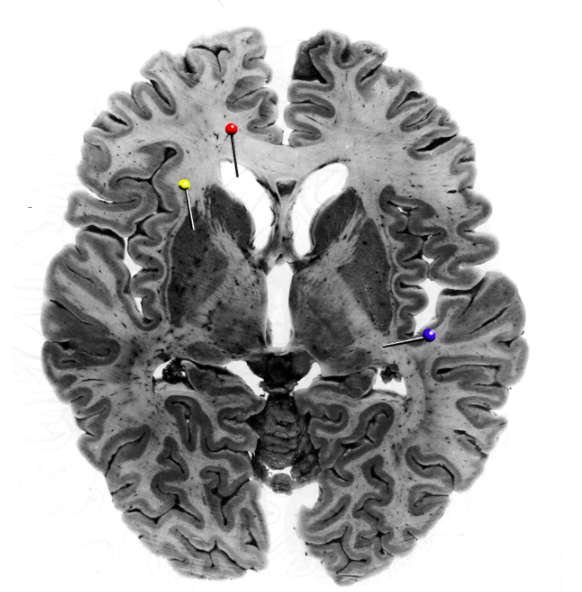

9

Q

In this horizontal brain slice, the yellow pin is in

the thalamus

the caudate nucleus

the putamen

the globus pallidus

A

putamen